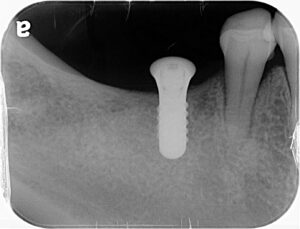

今回もコンピュータガイドを使って1本1本埋入位置を確認していきます。インプラントを埋める本数やデザインは最も好ましい条件から最低限の条件まで提示し、患者さんと相談の上進めていきます。今回は3本のインプラントを埋入しました。

ガイドを作成し、適切な位置に埋入します